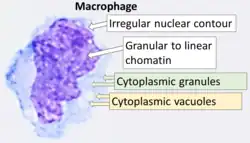

Cytology of a macrophage with typical features. Wright stain. | |